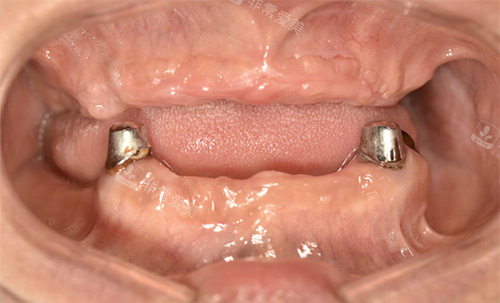

穿颧穿翼种植全口

All-on-4种植适合哪些缺牙人群?凯尔口腔做这项技术有优势吗?

All-on-4是半口/全口缺失的“较高的效率解决方案”,凯尔口腔在这项技术上的优势很明显:

适用人群广,骨量要求低:传统半口种植可能需要8-10颗植体,All-on-4仅用4颗植体,通过倾斜植入避开骨量不足区域,即使牙槽骨条件一般也能做,减少植骨需求。

当天种牙当天用,省时省心:手术当天就能完成植体植入和临时牙冠佩戴,不用等3-6个月骨结合期,不影响正常吃饭,尤其适合想快速修复咀嚼功能的患者。